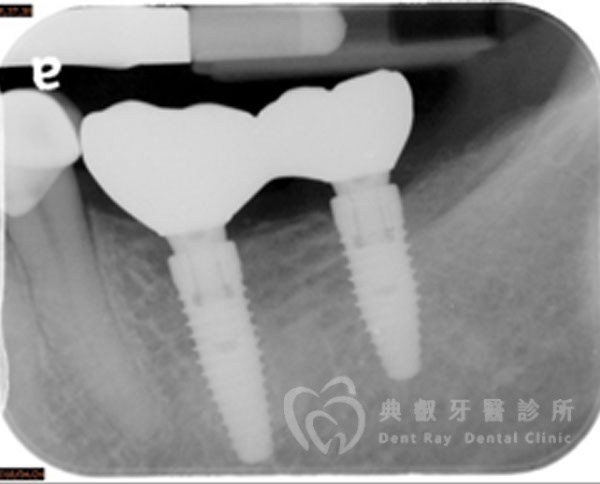

植牙案例三